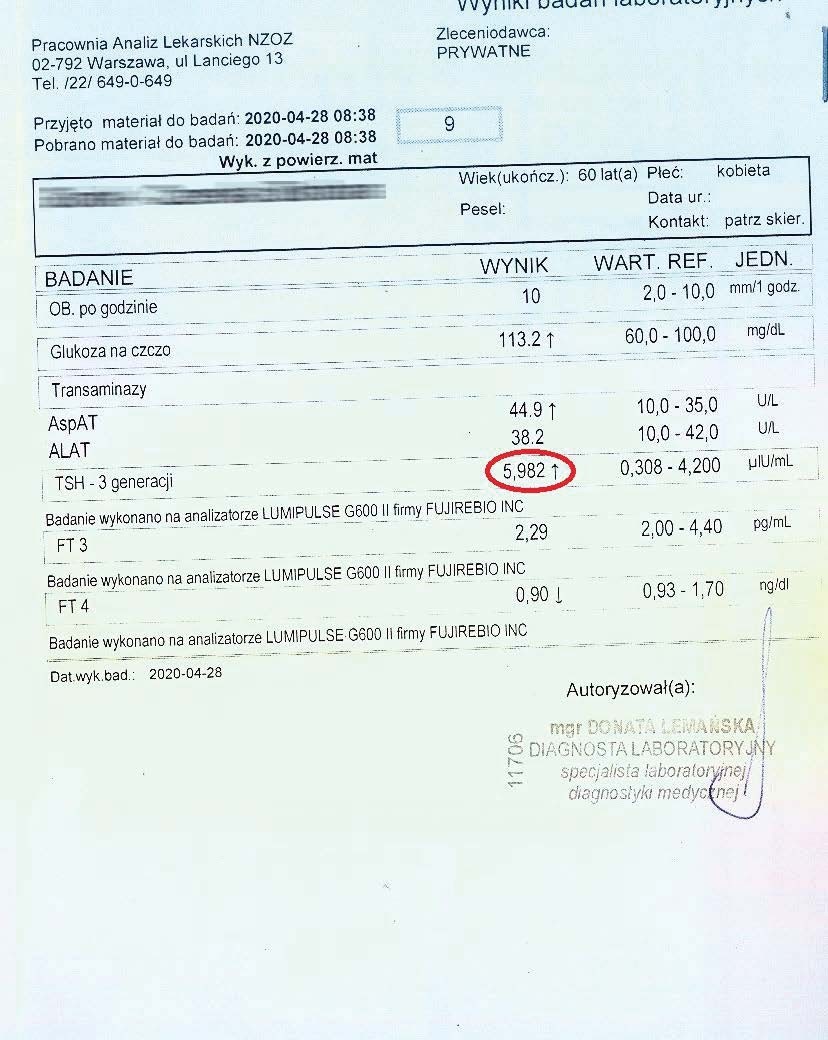

PRZYKŁAD EFEKTU PREPARATU NA NIEDOCZYNNOŚĆ TARCZYCY

Kobieta lat 59 z niedoczynnoscią tarczycy, bez przyjmowania lewotyroksyny. Kobieta przyjmowała preparat przez okres ponad 3 miesięcy. Przy zachowaniu naturalnego cyklu komórkowego i stałemu stymulowaniu mitochondriów osiągneła następujące wyniki kuracji:

Po zaobserwowaniu znacznej poprawy w ogólnym samopoczuciu, kobieta postanowiła wykonywać badania ze zwiększoną częstotliwością oraz kontrolę prób wątrobowych.

Po kolejnych dwóch miesiącach kobieta ponownie wykonała badania. Widoczne są: spadek TSH, obniżenie stanu zapalnego jak i spadek markeru wątrobowego GGTP.

Sukcesywnie co 2 miesiące można zaobserwować stały spadek parametrów zarówno wątroby jak i tarczycy. Kolejne badania potwierdzały dalszy spadek parametrów.

Po ponad roku kuracji badania wykazały dalszy postęp wycofania autoimmunologi tarczycy, potwierdzone również badaniem USG narządu.

Preparat wpływając na odbudowę mitochondriów zapewnił podłoże energetyczne do produkcji hormonów i odbudowy narządu. Brak ingerencji farmakologicznej wykazuje skuteczność nawet w podeszłym wieku, gdzie regeneracja jest wolniejsza a reakcje anaboliczne w znacznym stopniu spowolnione. Można zaobserwować także działanie ogólnoustrojowe obserwując spadek markeru wątroby, co jasno wykazuje poprawę funkcjonowania całego organizmu.